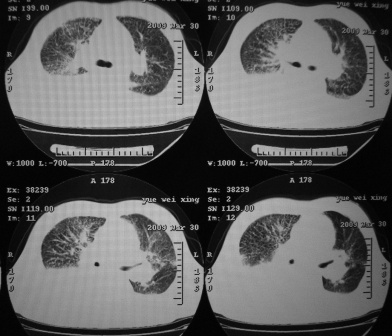

xx 男 43岁

右肺下叶支气管中断闭塞,右下肺见不规块影,并胸腔积液,考虑肺中央型肺癌继发下叶不张,\\双侧胸腔积液,心包积液。

右侧中央型肺癌伴右肺下叶不张,双肺及纵隔淋巴转移,双侧胸腔积液,心包积液。

1)考虑右侧中央型肺癌伴右肺下叶不张,双肺及纵隔淋巴转移。2)双侧胸腔积液,以右侧为甚。3)心包积液。

考虑右侧中央型肺癌伴右肺下叶不张,双肺及纵隔淋巴转移,双侧胸腔积液。不除外结核。

考虑右肺下叶中心性肺癌并纵隔淋巴结、双肺转移伴右肺下叶阻塞性肺不张;双侧胸水,右侧为著;心包积液